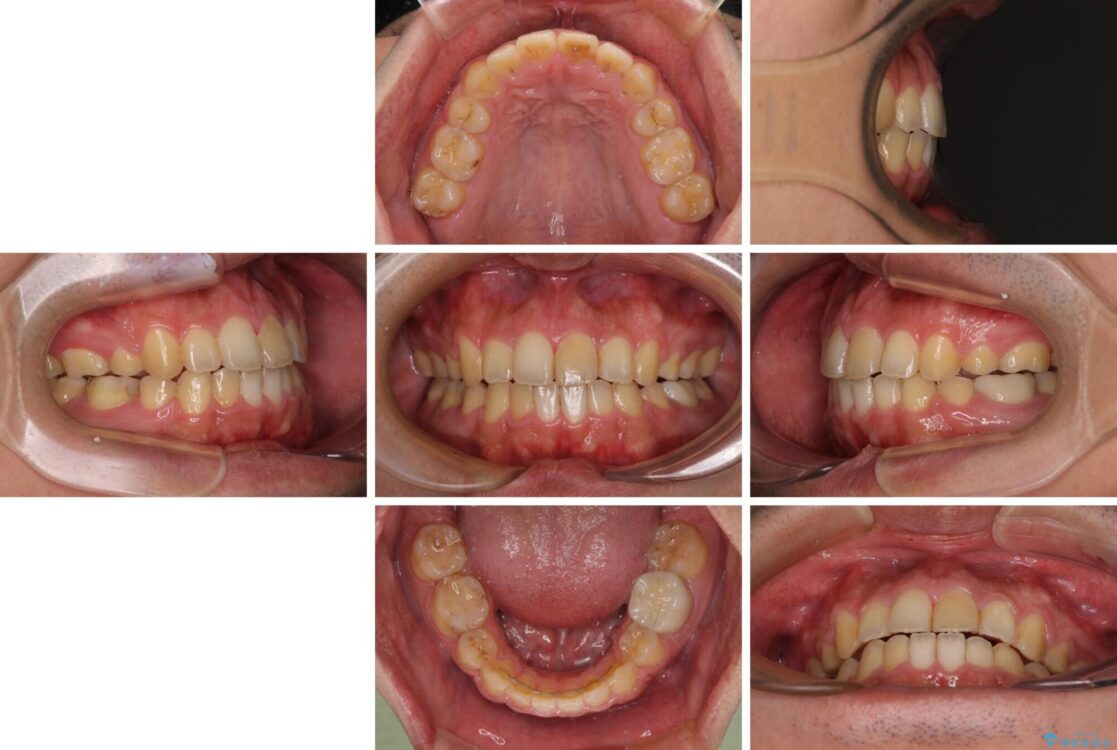

高校時代に行った抜歯矯正が後戻りをしたとのことで来院された患者様です。

治療前

• 後戻りでデコボコの前歯 インビザライン矯正治療 治療前画像